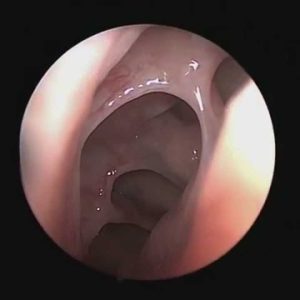

What The Sinuses Look Like After They Have Healed From Prior Sinus Surgery